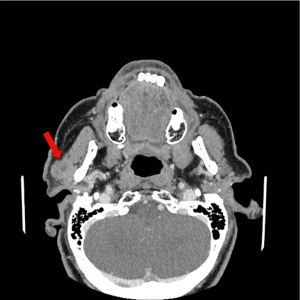

The right parotid gland tumor showed almost identical “basaloid” morphology as the BCC of the left eyelid, except that there were incomparably more features of keratinization evinced in keratin pearls formation (Figure 3). However, the manner of tumor growth of the right salivary gland was more typical for a newly formed cancerous lesion than for a metastasis focus, and with any possibility that both tumors could show anatomical continuity led to conclusion that the right salivary gland tumor was an independent, primary focus of the BSCC pT3N0Mx, stage II.